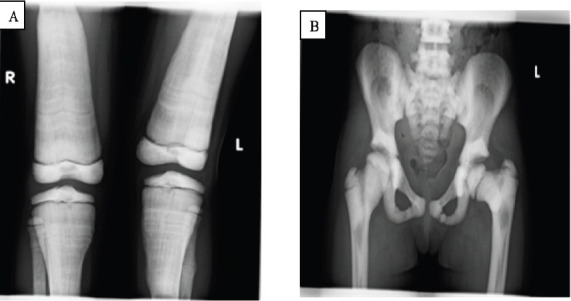

Case presentation: The patient is an eight-year-old girl who came to our hospital with complaints of bilateral arm swelling and visual disturbances for four years and a history of fracture of the left lower extremity two years before presentation. Physical examination revealed nontender bilateral arm swelling and a shorter left leg. The laboratory tests were within normal limits. A skeletal radiograph showed typical radiographic features of osteopetrosis.